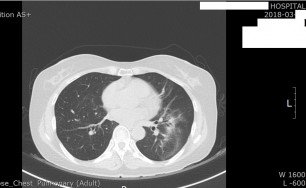

기흉